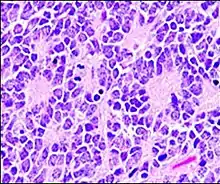

Micrograph of perivascular pseudorosettes

Perivascular pseudorosette

A perivascular pseudorosette consists of a spoke-wheel arrangement of cells with tapered cellular processes radiates around a wall of a centrally placed vessel. The modifier “pseudo” differentiates this pattern from the Homer Wright and Flexner-Wintersteiner rosettes, perhaps because the central structure is not actually formed by the tumor itself, but instead represents a native, non-neoplastic element. Also, some early investigators argued about the definition of a central lumen, choosing “pseudo” to indicate that the hub was not a true lumen but contained structures. Nevertheless, this pattern remains extremely diagnostically useful and the modifier unnecessarily leads to confusion. Perivascular pseudorosettes are encountered in most ependymomas regardless of grade or variant. As such, they are significantly more sensitive for the diagnosis of ependymomas than true ependymal rosettes. Unfortunately, perivascular pseudorosettes are also less specific in that they are also encountered in medulloblastomas, PNETs, central neurocytomas, and less often in glioblastomas, and a rare pediatric tumor, monomorphous pilomyxoid astrocytomas.[2]